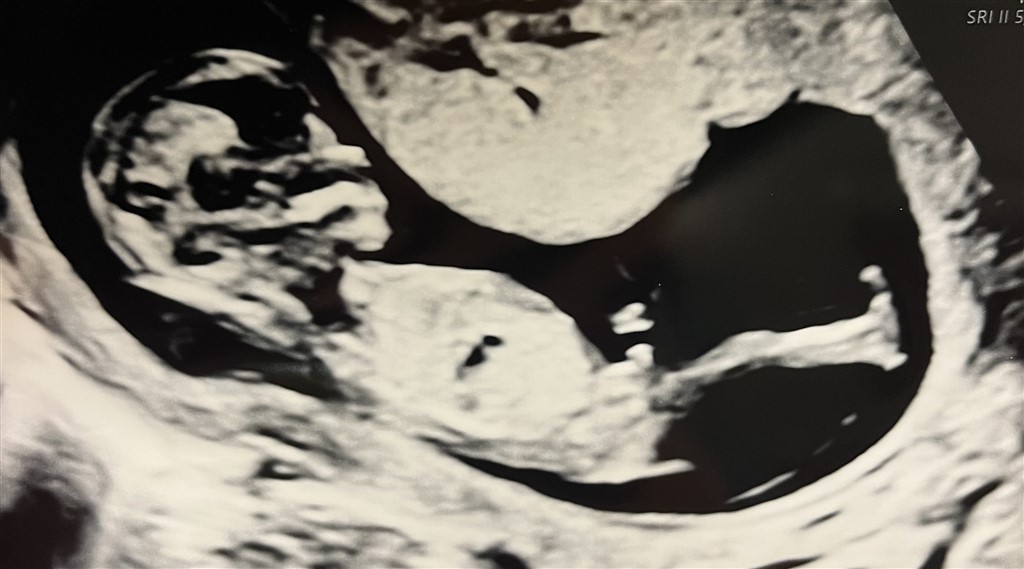

Jeg er 13+3 i dag og synes, at jeg til scanningen så en tydelig tissemand. Er vi enige om, at det her ligner en dreng mistænkelig meget?

Vedhæftede fotos (klik for at se i fuld størrelse)

Jo, jeg vil med 100% sikkerhed også sige dreng